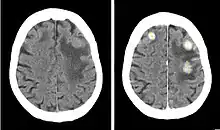

Iopentol (trade name Imagopaque) is a pharmaceutical drug that was used as a radiocontrast agent for X-ray imaging in Europe.[1]

Uses included arteriography (imaging of arteries), venography (imaging of the veins) and CT scan enhancement, urography (imaging of the urinary system), arthrography (imaging of the joints), endoscopic retrograde cholangiopancreatography (ERCP; imaging of bile and pancreatic duct), hysterosalpingography (imaging of the uterus and fallopian tubes), and gastrointestinal studies.[1]

Iopentol is an iodine-containing, water-soluble radiocontrast agent. The iodine atoms readily absorb X-rays, resulting in a higher contrast of X-ray images. It has a low osmolality, meaning that the solution has a relatively low concentration of molecules; this is usually associated with fewer adverse effects than high-osmolality contrast agents.[1][2]

A phase III clinical trial concluded that iopentol produces images of a similarly high quality as iohexol, and that it is equally well tolerated by patients.[1]